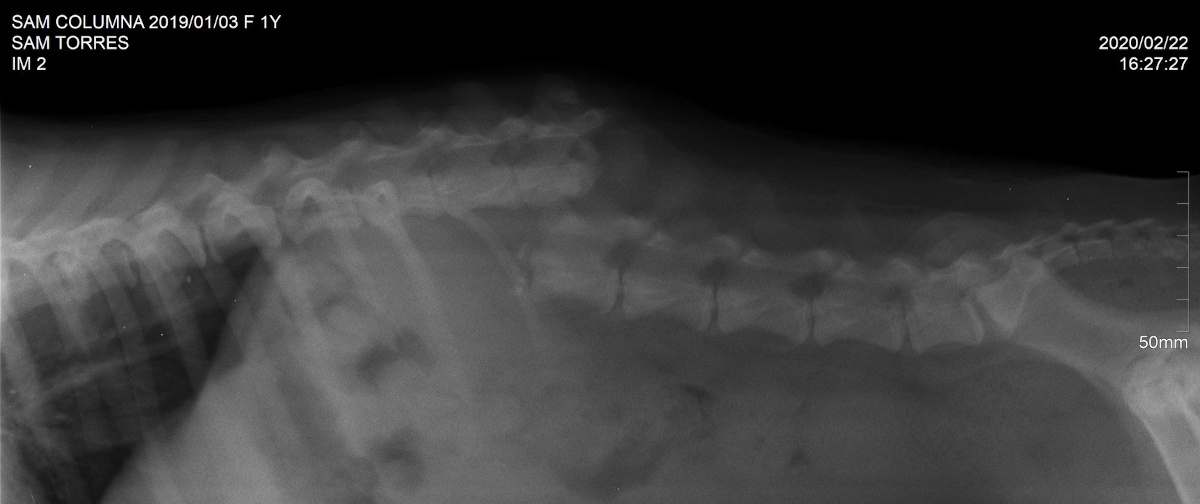

As a young dog, Semi Sweet suffered a devastating injury, probably from being hit by a car on the Tijuana streets. This accident resulted in a broken back, her spine broken in two. The injury left her paraplegic, unable to use her hind legs. Yet, as a street dog on her own, Semi still tried to live, despite her injury, and she dragged herself, attempting to find food and water. Semi never gave up hope, determined to survive but suffered road rash, wounds, pressure sores and swelling on her legs, feet and seat from dragging herself along the roads.